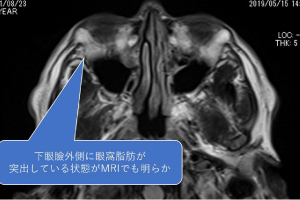

MRI horizontal section T1-weighted

There was clearly a large fat protrusion and both lower and upper eyelids were bulging.

In this case, it is not just the surface fat that is the problem, but also the fat behind it.

There was clearly a large fat protrusion and both lower and upper eyelids were bulging.

In this case, it is not just the surface fat that is the problem, but also the fat behind it.